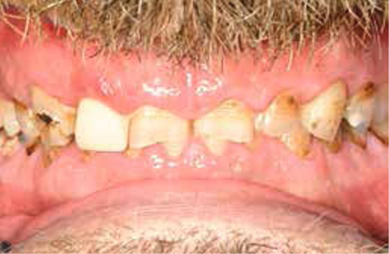

Afb. 2

Frontaal aanzicht van de dentitie.

Bij het extraoraal onderzoek zie ik een lichte hypertrofie van de m. masseter. Intraoraal tref ik een ernstig versleten dentitie aan waarbij de slijtage niet passend bij de leeftijd kan worden genoemd (afbeelding 2-7 en tabel 1) .